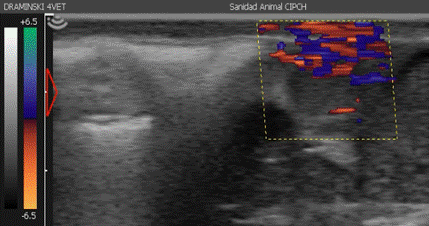

Evaluación ultrasonográfica del cuerpo lúteo (Doppler Color). Fue realizado el día 19 post IATF utilizando el equipo Draminski 4Vet®, primeramen-te, identificando el CL solo con modo B para deter-minar el diámetro (mm) y volumen (mm3), segui-damente, se activó el modo Doppler Color para determinar el área vascular luteal (AVL %) que se determinó en porcentaje, una vez almacenada el cinestore (video corto de la evaluación del CL) fue analizado con el programa Image J® en un ordenador, la metodología fue realizada según lo recomendado por Acosta et al.11.

Figura 1 Evaluación de la ecografía Doppler Color en un cuerpo lúteo de vacas Criollas (día 19 post IA)

Las características del CL fueron de 7.96 mm de diámetro con tamaños que fluctuaron entre 6.82 y 9.10 mm, así mismo, el volúmen del CL fue de 0.23 mm3 con intérvalos que fueron desde 0.16 a 0.31 mm3, la característica tomada con ultrasonografía Doppler fue el AVL evaluada en porcentajes siendo esta en promedio de 20.96 % con intervalos que fueron desde 13.16 a 28.76 %, todas estas características fueron determinadas con un 95 % de confiabilidad. La evaluación Doppler Color, Figura 1.

Para la evaluación del CL se evaluó su volumen observándose diferencias que fue referenciada por diversos autores, que reportaron diámetros de CL menores en vacas Criollas en comparación a otros estudios realizados en otras razas como la Holstein, teniendo las mismas razones halladas tras comparar el diámetro de CL13,14,17,25. Además, se evaluó Doppler Color en condiciones de altitud se reportó en promedio un 20.96 % de AVL, que se interpreta como el porcentaje de irrigación sanguínea en relación al área total del CL, no existiendo alguna diferencia marcada entre aquellas vacas que quedaron preñadas y vacías respectivamente por tal motivo este porcentaje es descriptivo indicando que en vacas Criollas a los 15 días post IA o post celo reportaron un CL con una irrigación aproximada de 20.96 %, este método mide la velocidad e intensidad del flujo sanguíneo y el número de glóbulos rojos que se mueven a través de los vasos sanguíneos por min19,26, además es necesario indicar que la coloración que el Doppler Color tiene como principio que la coloración roja son aquellos vasos sanguíneos que se están acercando hacia el transductor, mientras que la coloración azul son los vasos sanguíneos que se alejan, todo ello al momento que se realizó el examen ecográfico25,27, comparado los resultados no se pudo reportar diferencias entre las vacas preñadas y no preñadas, debido a que el día de evaluación (19 días post IA) coincide con la regresión de CL de aquellas vacas que no pudieron quedar preñadas y en dicho proceso se ha estudiado de que antes de que ocurra la secreción de Prostaglandina F2α existe un aumento repentino de la irrigación sanguínea11,25 que podría ser tomada con una falso positivo (diagnosticando una vaca preñada como no preñada), así mismo, mencionan que la evaluación solo del flujo sanguíneo por ecografía Doppler fue insuficiente para diagnóstico, esta tendría que ser acompañada de evaluación de concentraciones de progesterona28. Finalmente, la tasa de preñez obtenida tras la evaluación ecográfica el día 30 post IA fue 6 vacas de 15 que fueron sincronizadas que representaría un 40%.